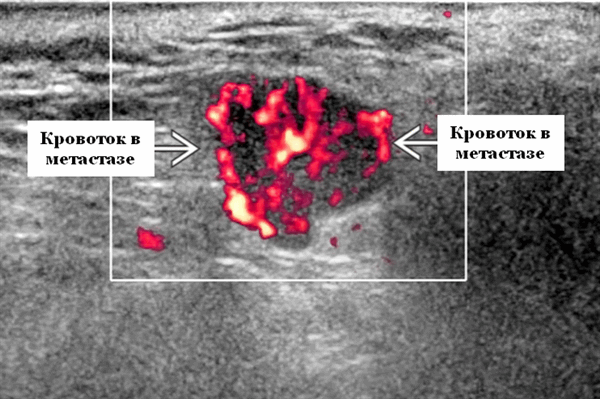

- Выраженная внутриузловая гиперваскуляризация.

Энергетический допплер. Выраженная внутриузловая гиперваскуляризация

Энергетический допплер. Внутриочаговая васкуляризация. Хаотический / дезорганизованный или преимущественно периферический кровоток